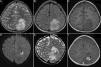

An eight-year-old girl was admitted to our hospital with complaints of vomiting and afebrile seizures. Her history revealed malaise, loss of appetite, and recurrent afebrile generalized tonic seizures lasting for 8–10min in the past month. Her medical history was unremarkable with no history of trauma. On admission, she had no fever, nor any neurological deficits and the systemic examination was unremarkable except for a systolic murmur. Laboratory tests included complete blood count and blood chemistry within normal limits except for an elevated C-reactive protein (CRP) of 74mg/L. Electrocardiography (ECG) and echocardiography were normal. The awake and asleep EEG revealed slowing of background rhythm over the left parieto-occipital area with no epileptiform discharges. She had two episodes of afebrile generalized tonic seizures at the time of hospitalization and phenytoin was started. Cranial magnetic resonance imaging (MRI) showed a multiloculated lesion 50mm×40mm in size, hypointense on T1 and hyperintense on both T2 and fluid-attenuated inversion recovery (FLAIR) images at the left parieto-occipital region with peripheral edema. Contrast enhancement was also suggestive of an abscess formation (Fig. 1). Lumbar puncture was not performed because of the large mass compatible with brain abscess and the surrounding extensive edema. Ceftriaxone, metronidazole, and mannitol were added. The case underwent burr hole drainage and 40mL of purulent material was drained. One month after the first procedure, parieto-occipital craniotomy was performed to evacuate the abscess that had recurred. No microorganisms were isolated from the abscess cultures. Blood cultures and serological test for hydatid cysts were negative. Brucella agglutination test was positive at 1:1280 titers in blood. When the patient's history was questioned in detail, it was learned that her family was living in the countryside, her father was a farmer and brucellosis has been diagnosed in one of her sisters. Intravenous ceftriaxone was given for 10 days followed by oral rifampicin and trimethoprim-sulfamethoxazole. The blood brucella agglutination titer was 1:320 at the second month and long-term antibiotic treatment was planned with rifampicin and trimethoprim-sulfamethoxazole.

Axial T2-weighted (A) and FLAIR images (B) revealing hyperintense cortical-subcortical 50mm×40mm lesion with surrounding edema. Axial T1-weighted (C), diffusion-weighted (DWI) (D), apparent-diffusion coefficient (E) and T1-weighted post-contrast images with peripheral ring-like enhancement (F) confirming abscess formation.